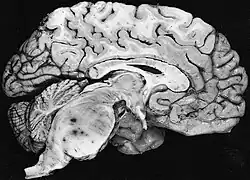

Diffuse fibrillary astrocytomas arising in the brain stem favor the pons: The tumor here produces the classic hypertrophy of the affected region. | |